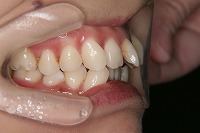

26歳1か月

右

前歯が出ていて歯並びが悪い事を主訴に来院された、26歳1か月の女性です。診断「歯と歯槽基底の大きさの不調和による叢生」上顎は右側第1小臼歯と左側の犬歯、下顎は抜歯をせず治療を行いました。